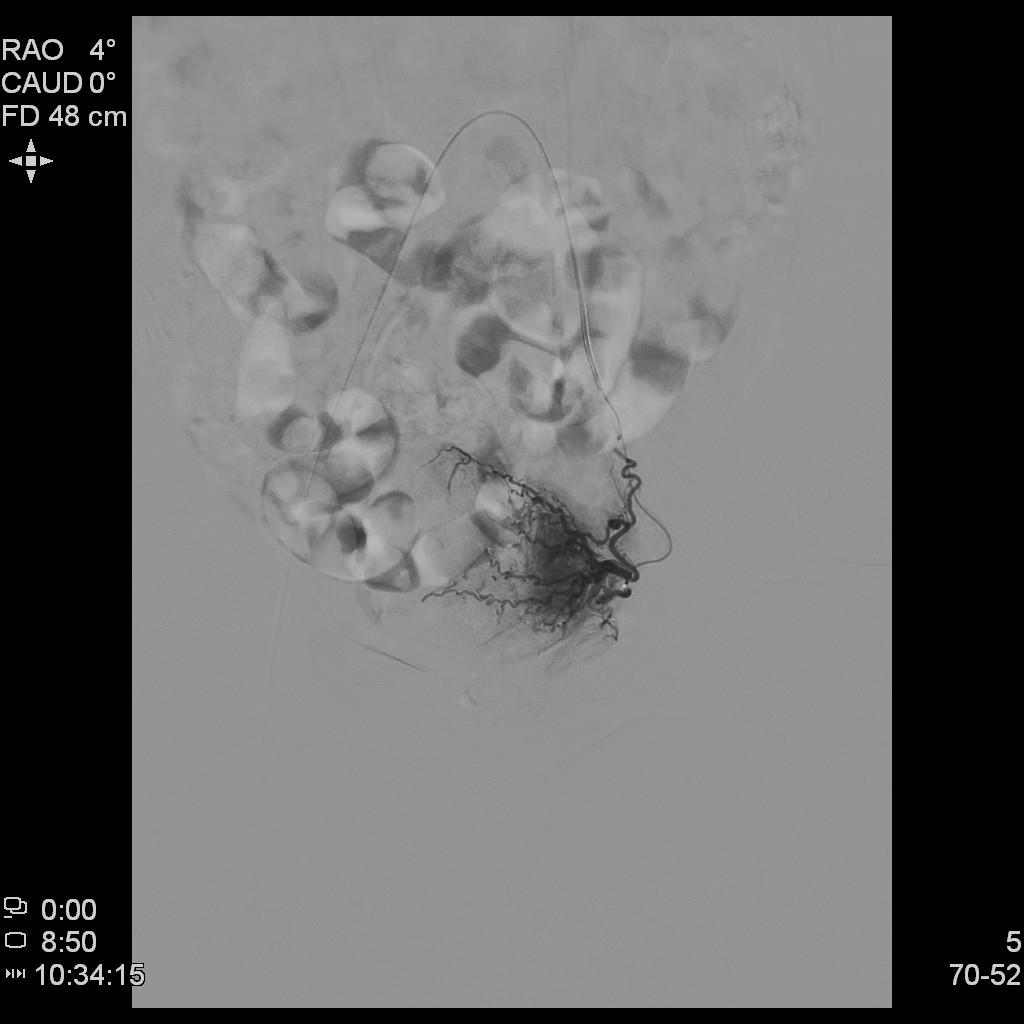

例2

中年患者,患有“子宫腺肌瘤”7年余,长期受痛经、月经量增多困扰,严重影响生活质量。经多处求医,经历药物调理、“曼月乐”宫腔植入、“海扶刀”消融术等多种治疗,痛经、月经量多等情况一直无法有效缓解,日渐严重。

- 术前MRI检查显示子宫明显增大。

术前MRI检查显示子宫明显增大

- 插管至右侧子宫动脉,显示子宫右侧病灶情况

右侧子宫动脉造影

- 插管至左侧子宫动脉,显示子宫左侧病灶情况

左侧子宫动脉造影

- 术后4个月复查,子宫明显缩小,腺肌瘤明显坏死吸收,相关症状基本消失。

术后复查MRI显示子宫明显缩小,腺肌瘤明显坏死吸收